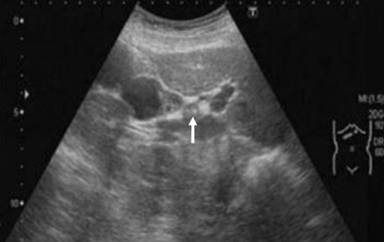

A 60-year-old woman presenting with no symptoms and no history of biliary colic underwent routine abdominal ultrasonography (US) as part of a medical check-up. The US results revealed a nodular protrusion sized 15 mm at the neck of the gallbladder (Figure 1). Despite this abnormality, the patient’s abdomen was unremarkable on physical examination. Neither the results of routine blood tests, which revealed serum carcinoembryonic antigen concentration (CEA) and CA 19-9 levels within normal ranges, nor magnetic resonance cholangiopancreatography (Figure 2), which detected no pancreaticobiliary maljunction, indicated any other abnormality. Although the nodular protrusion seemed likely to be a lymph node, gallbladder cancer could not be ruled out because it was a wide-based protrusion. To determine whether the protrusion was cancerous, laparoscopic cholecystectomy was performed using the standard 4-port technique for diagnosis and treatment. The intraoperative findings indicated that the protrusion was likely not cancerous. The postoperative course was uneventful and the patient discharged on the fourth postoperative day without any complications.

Figure 1. Abdominal ultrasound showing thickened lesion on neck of gallbladder (arrow). |